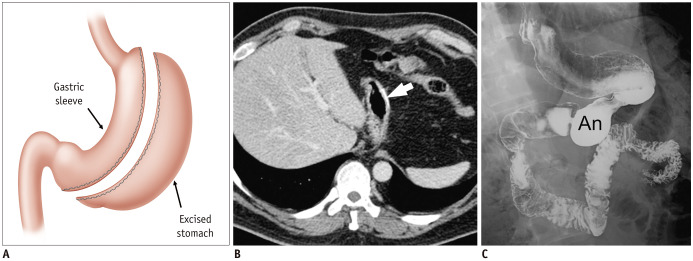

Fig. 18. Sleeve gastrectomy.

A. Illustration shows normal surgical anatomy after sleeve gastrectomy. Stomach is resected along greater curvature of fundus, body, and proximal antrum, producing narrow, banana-shaped gastric sleeve along lesser curvature. B. On axial CT image, metallic suture (arrow) is observed in new greater curvature of stomach. C. Contrast swallow study shows decrease in gastric volume with tubular morphology. Note that distal antrum (An) is intact.

Gastric leaks are potential complications and most commonly occur from the proximal end of the staple line near the gastroesophageal junction (94,95,96,97). Contrast filled within non-excised fundus may be mistaken for an extraluminal leak. Gastric stricture is a rare complication, which may develop from intra-operative stapling error, particularly at the incisura angularis (98). Contrast swallow study or endoscopy can be used for this complication. CT may show acute angulation of the gastric sleeve at the level of the incisura angularis (99).